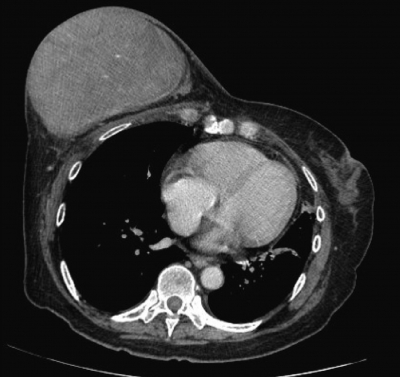

右乳房腫瘤は長径 17 cm で、弾性軟、胸壁への固定を認めない。皮膚には発赤や腫瘤の浸潤を認めない。腋窩リンパ節を触知しない。胸部 CTを別に示す。